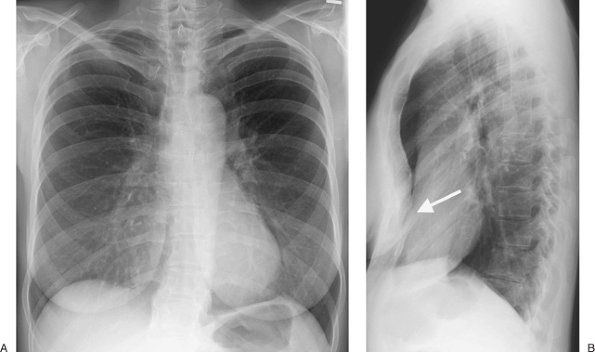

FIGURE 9-15. Empyema. A: PA chest radiograph of a 55-year-old man shows a large left pleural effusion, compression of the upper lung, and collapse of the lower lung. B: CT shows an elongated ovoid collection of fluid in the left pleural space and collapse of the adjacent lung.